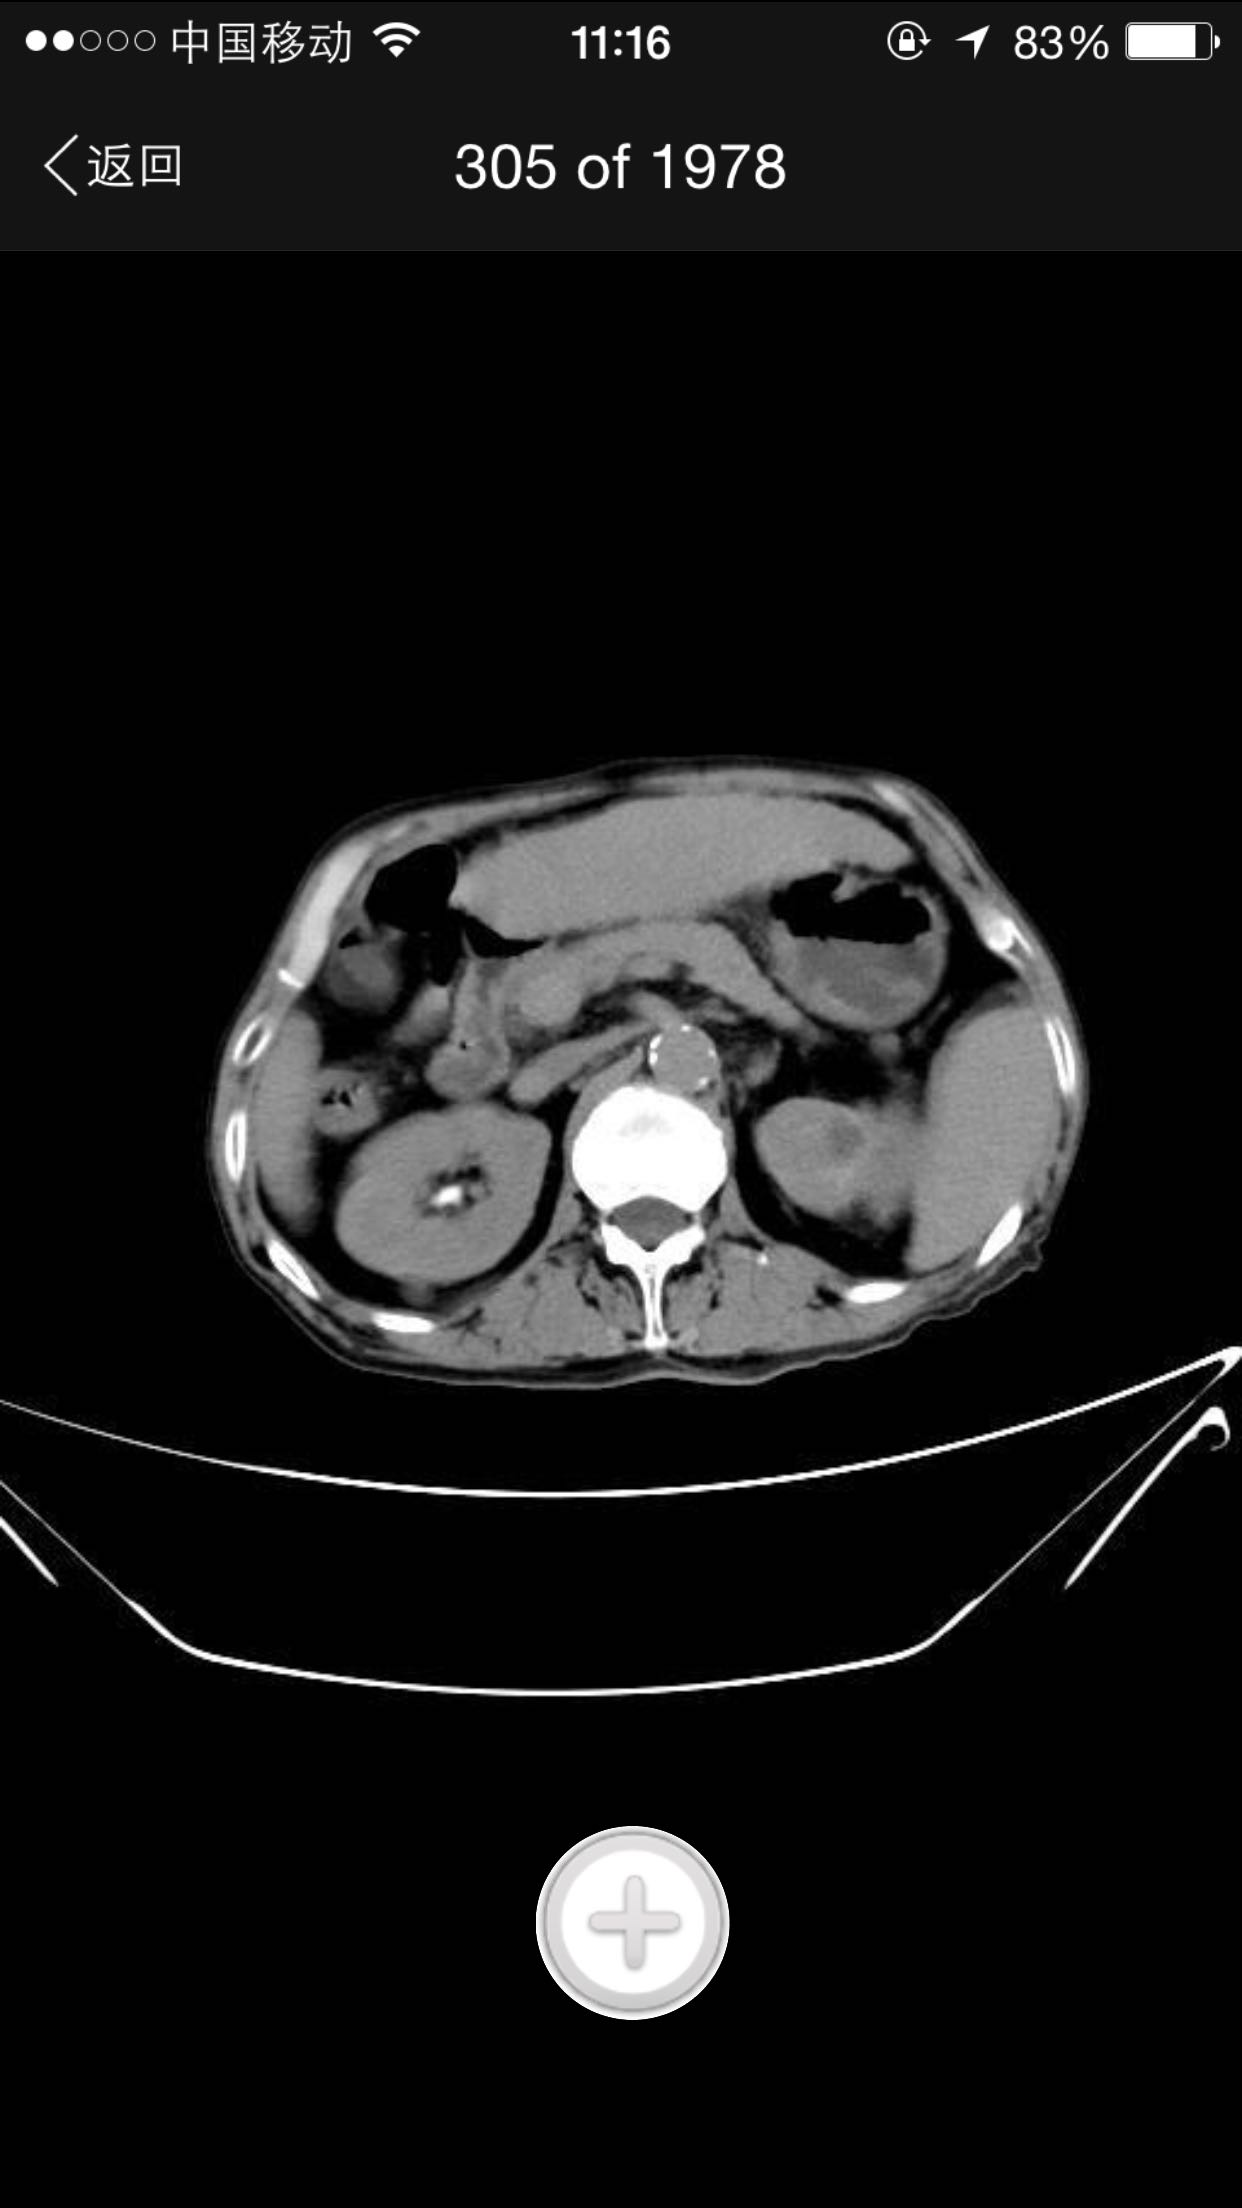

排尿困难,尿潴留入院。诊为前列腺增生症,拟行手术治疗。完善术前检查,泌尿系CT检查发现左肾占位,左肾结石并左肾重度积水,左肾萎缩等。既往患者肺结核病史,服药控制半年余。

查体:腹平软,无压痛及反跳痛,无肾区叩痛,肛诊前列腺明显增大,中央沟消失,无硬结,无压痛。术前强化CT提示左肾癌。

术前诊断:1、左肾癌2、左肾结石3、左肾积水4、左肾萎缩5、前列腺增生6、肺结核 入院后完善检查,拟行TURP,因发现左肾癌,改为先行肾手术。患者左肾癌,同时左肾结石,肾萎缩,决定行根治性肾切除,拟腹腔镜下手术,患者家属不同意,改开放手术,全麻下行根治性左肾切除。术后剖开标本如下图,肿瘤位于肾上极,中间黑色为结石。